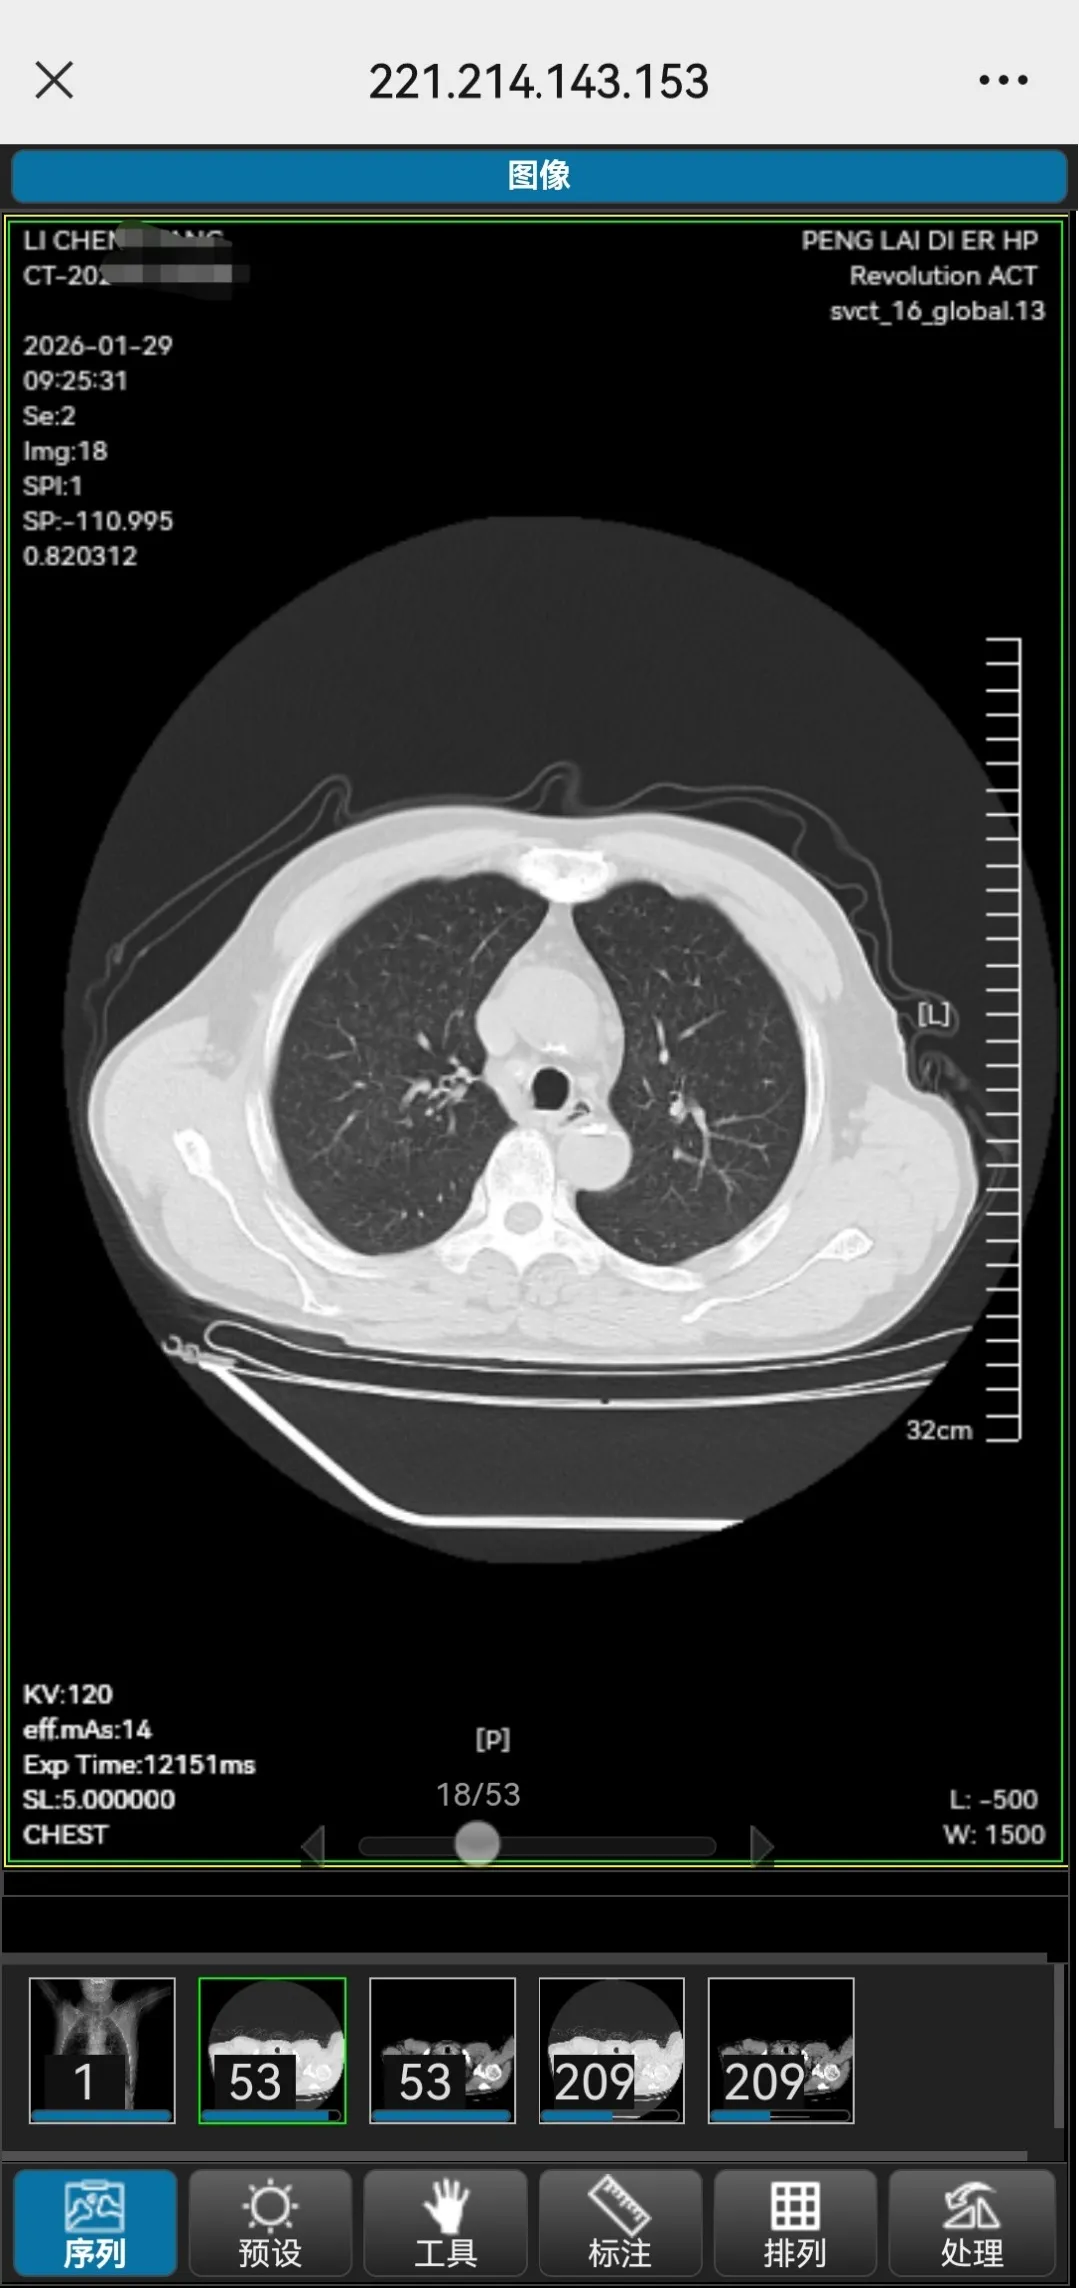

为进一步提升医疗服务效率,优化患者就医体验,烟台市蓬莱第二人民医院“云胶片”服务正式上线! 患者完成放射检查后,无需等待实体胶片打印、费力携带保管,一部手机就能轻松查看高清影像!

1.手机随时查:检查完成后,您只需通过手机,即可随时随地查看高清的原始影像图像和详细的诊断报告。